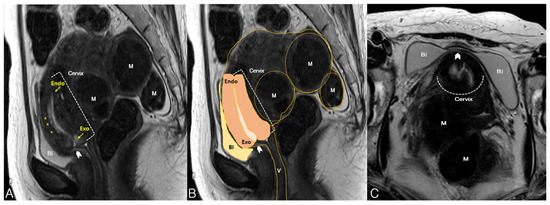

Uterine incarceration is rare, but it can cause serious complications, in which the uterus is trapped in the pelvic cavity behind the sacral promontory. Fibroid uterus can cause urinary frequency and retention, which can result from compression of the urinary bladder with an enlarged fibroid uterus and the compression of the bladder neck or urethra, respectively. To our knowledge, there is no report on prolonged complete urinary obstruction because of an incarcerated uterus in nonpregnant women to date. A 51-year-old woman was referred for uterine myomas. She could not void for 30 months after she received an intradetrusor injection of botulinum toxin for urinary frequency management at the urology department of another hospital. She underwent clean intermittent catheterization for 30 months. She was referred to the gynecologic department for the evaluation of uterine myoma found on using abdominopelvic computed tomography. On physical examination, the uterine cervix was extremely displaced in the upward direction and was not exposed on speculum examination. Sonography and magnetic resonance imaging revealed that the urethra and the bladder neck were compressed by an extremely retroflexed fibroid uterus. Manual reduction of the incarcerated uterus failed; hence, we performed robot-assisted laparoscopic total hysterectomy with left salpingo-oophorectomy. She immediately urinated immediately after the operation and had normal urination at 1- and 48-month follow-up visits. Uterine incarceration by a fibroid uterus can cause complete urinary obstruction, as in this case. Uterine incarceration should be considered in women with urinary frequency or retention to avoid prolonged, serious complications. Full article

Show Figures

Figure 1